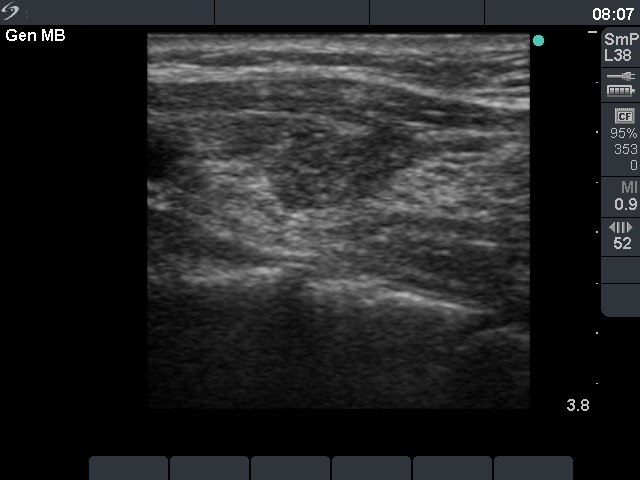

Second row: ultrasonographic pictures 6 weeks after the last session of sclerotherapy. The size of the lesion became 12x7x13 mm (width x depth x length).